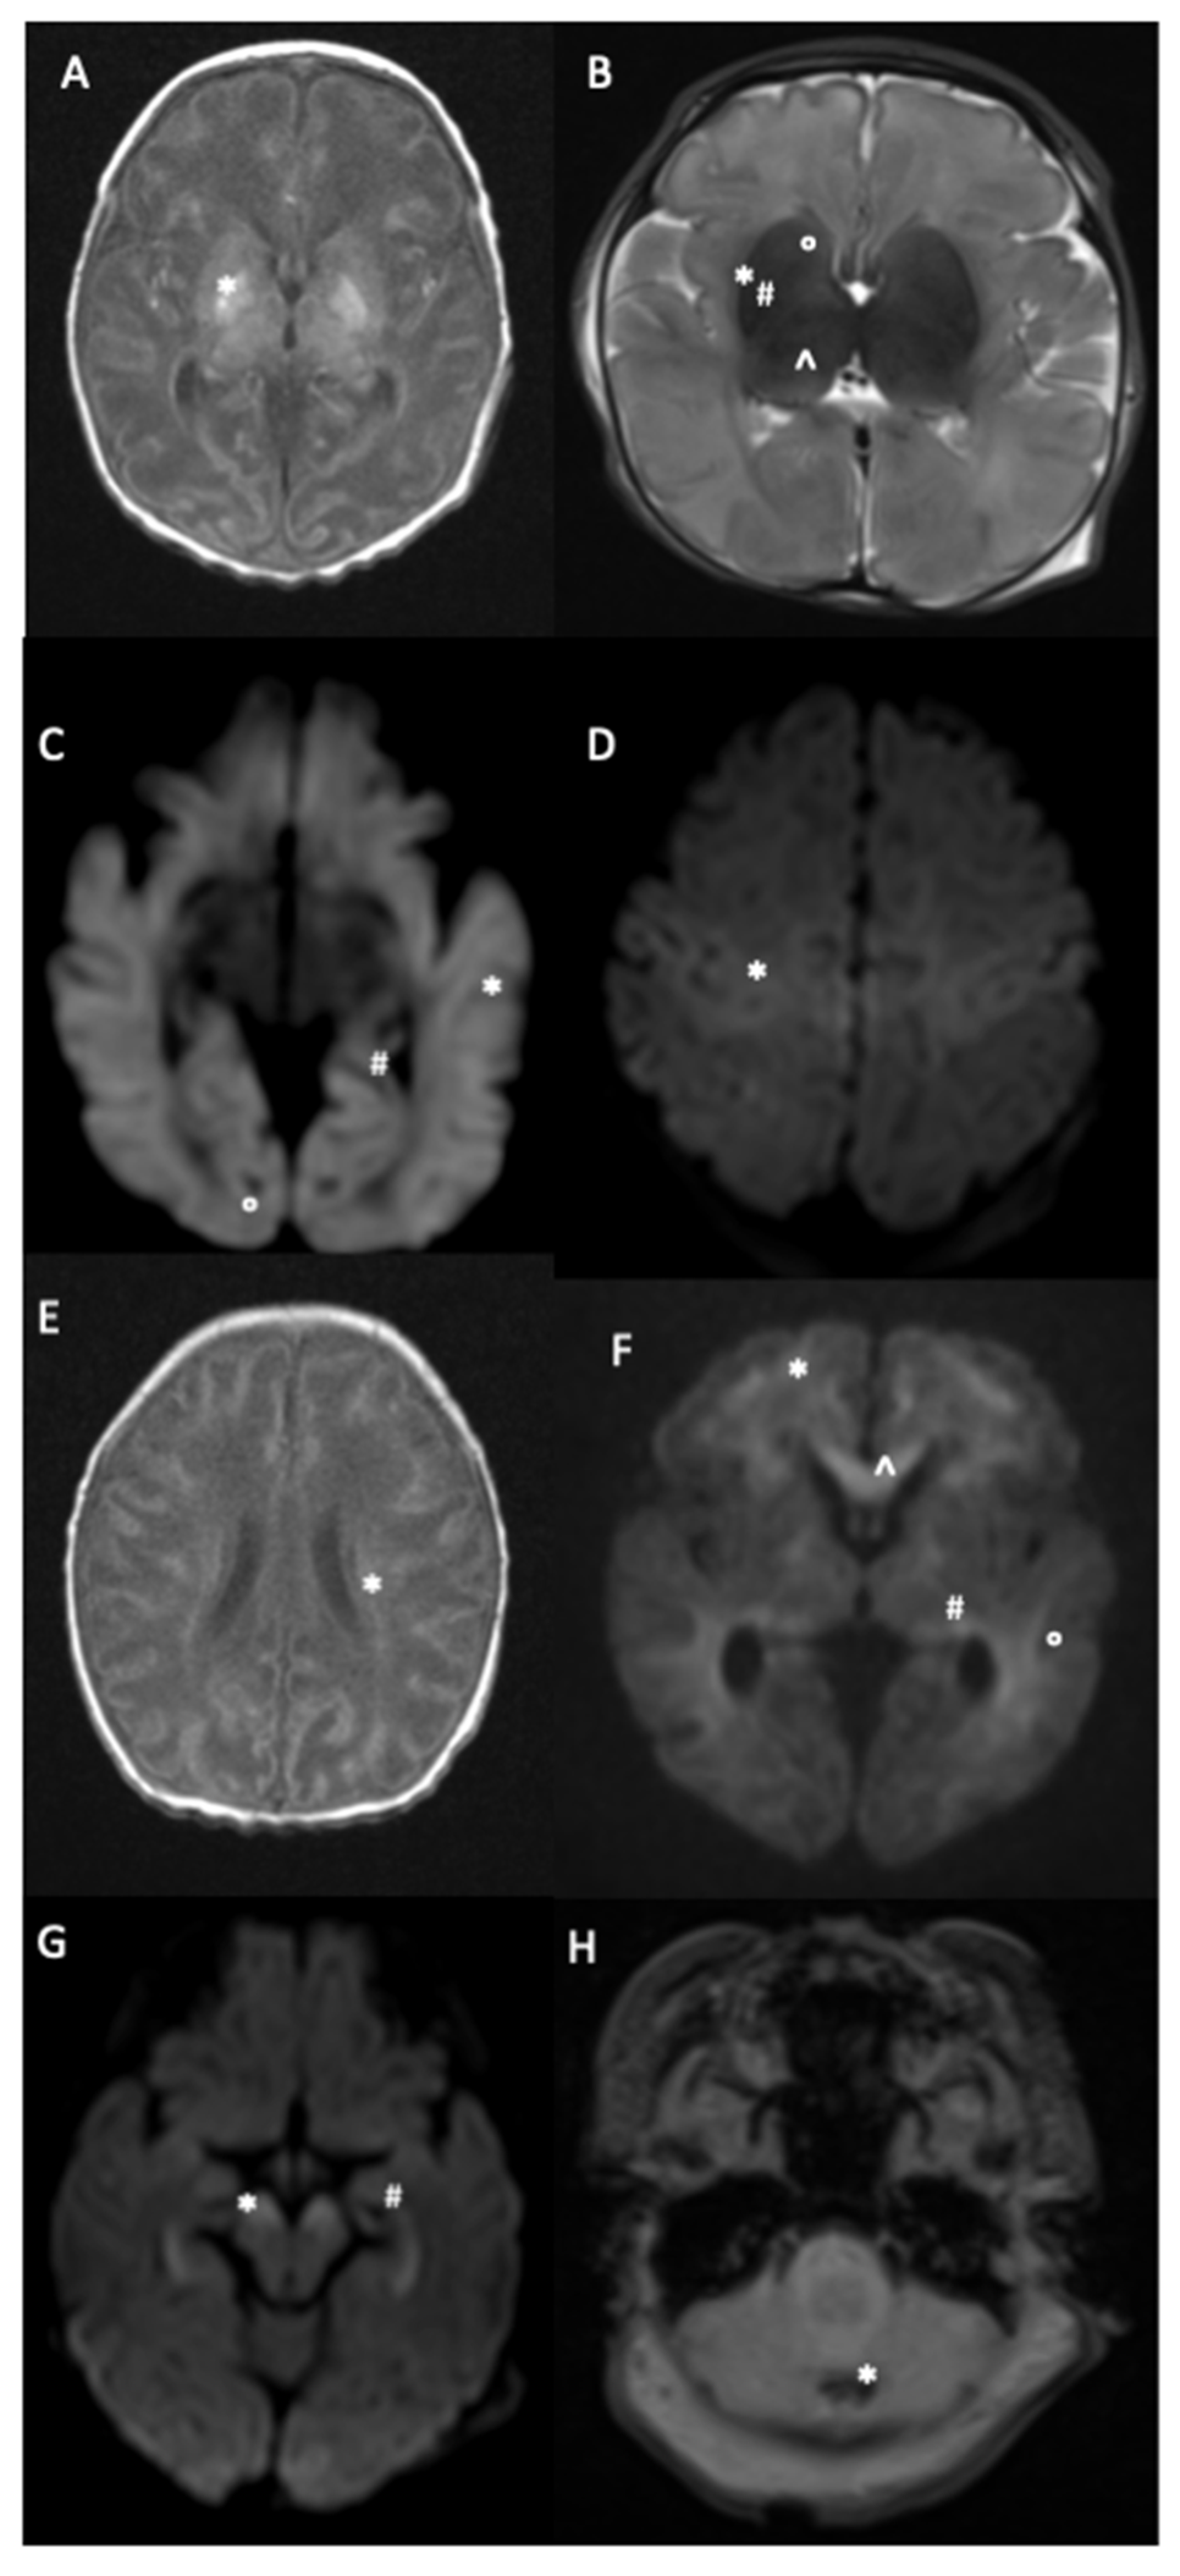

| BGT | 171/506 (33.8) | 157/466 (33.7) | 14/40 (35.0) |

| - Thalamus | 121 | 109 | 12 |

| - Globus pallidus | 93 | 84 | 9 |

| - Putamen | 85 | 78 | 7 |

| - Caudate nucleus | 59 | 52 | 7 |

| PLIC | 82/497 (16.5) | 72/456 (15.8) | 10/41 (24.4) |

| WM | 166/496 (33.5) | 148/456 (32.5) | 18/40 (45.0) |

| Cortex | 128/500 (25.6) | 114/459 (24.8) | 14/41 (34.2) |

| CC | 63/460 (13.7) | 56/422 (13.3) | 7/38 (18.4) |

| Brainstem | 44/501 (8.8) | 39/461 (8.5) | 5/40 (12.5) |

| Cerebellum | 24/491 (4.9) | 23/450 (5.1) | 1/41 (2.4) |

| BGT | 171/506 (33.8) | 94/236 (39.8) | 77/270 (28.5) |

| WM | 166/496 (33.5) | 85/231 (36.8) | 81/265 (30.6) |

| Cortex | 128/500 (25.6) | 73/231 (31.6) | 5/269 (20.5) |

| PLIC | 82/497 (16.5) | 50/230 (21.7) | 32/267 (12.0) |

| CC | 63/460 (13.7) | 35/227 (15.4) | 28/233 (12.0) |

| Brainstem | 44/501 (8.8) | 31/232 (13.4) | 13/269 (4.8) |

| Cerebellum | 24/491 (4.9) | 13/234 (5.6) | 11/257 (4.3) |